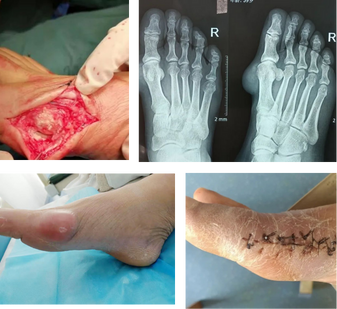

案例三

痛風石破潰且腐蝕關節,治療后行走自如

患者:趙先生/56歲

病情:一次睡夢中被腳部劇烈疼痛痛醒,右腳大拇指又紅又腫,服用止痛藥疼痛緩解,之后,大腳趾處時不時的還會疼痛,每次都是吃止痛藥,后來發現腳上長了一個包塊。

明陪伴—陪診服務平臺